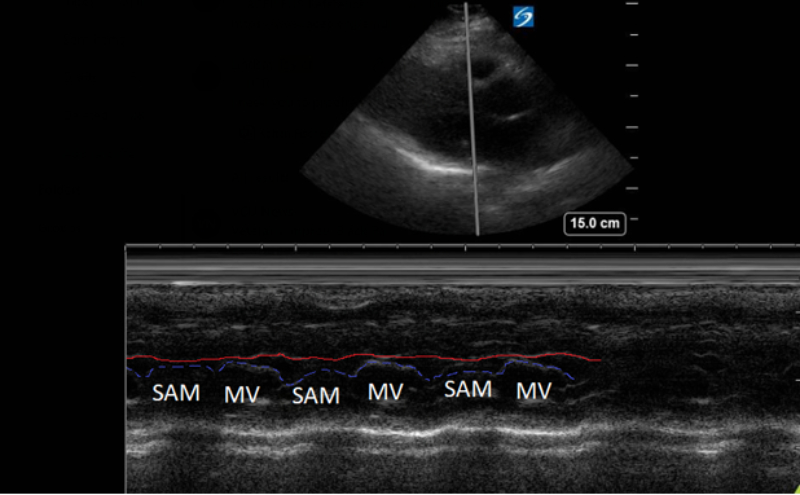

A point-of-care ultrasound was performed to evaluate for potential etiologies of syncope. The ultrasound displayed biventricular and interventricular septal hypertrophy (Figure 2), systolic anterior motion of the mitral valve (SAM, Figure 3), and a “dagger-like” continuous wave Doppler waveform emerging from the left ventricular outflow tract. (LVOT, Figure 4)

Figure 3. Parasternal long-axis view using M-Mode displaying SAM of the mitral valve against the interventricular septum (red line). Note how the mitral valve shifts anteriorly during the same period that the septum contracts posteriorly.

Hypertrophic obstructive cardiomyopathy (HOCM) refers to the common obstructive subset that affects 70% of patients with HCM.6 Left ventricular outflow tract obstruction (LVOTO) has been shown to be an independent predictor for adverse outcomes by multiple studies.7 Traditionally, systolic anterior motion (SAM) of the mitral valve was thought to be pathognomonic for HCM. Recent studies have shown that of the HCM patients with SAM, 25-50% will have LVOTO.8 Using ultrasound, SAM is observed in the parasternal long-axis using M-mode over the anterior leaflet of the mitral valve. The time the valve is contact with the septum quantifies disease severity.

1) Mild: brief SAM without septal contact

2) Moderate: septal contact < 1/3 of systolic period

3) Severe: septal contact > 1/3 of systolic period9